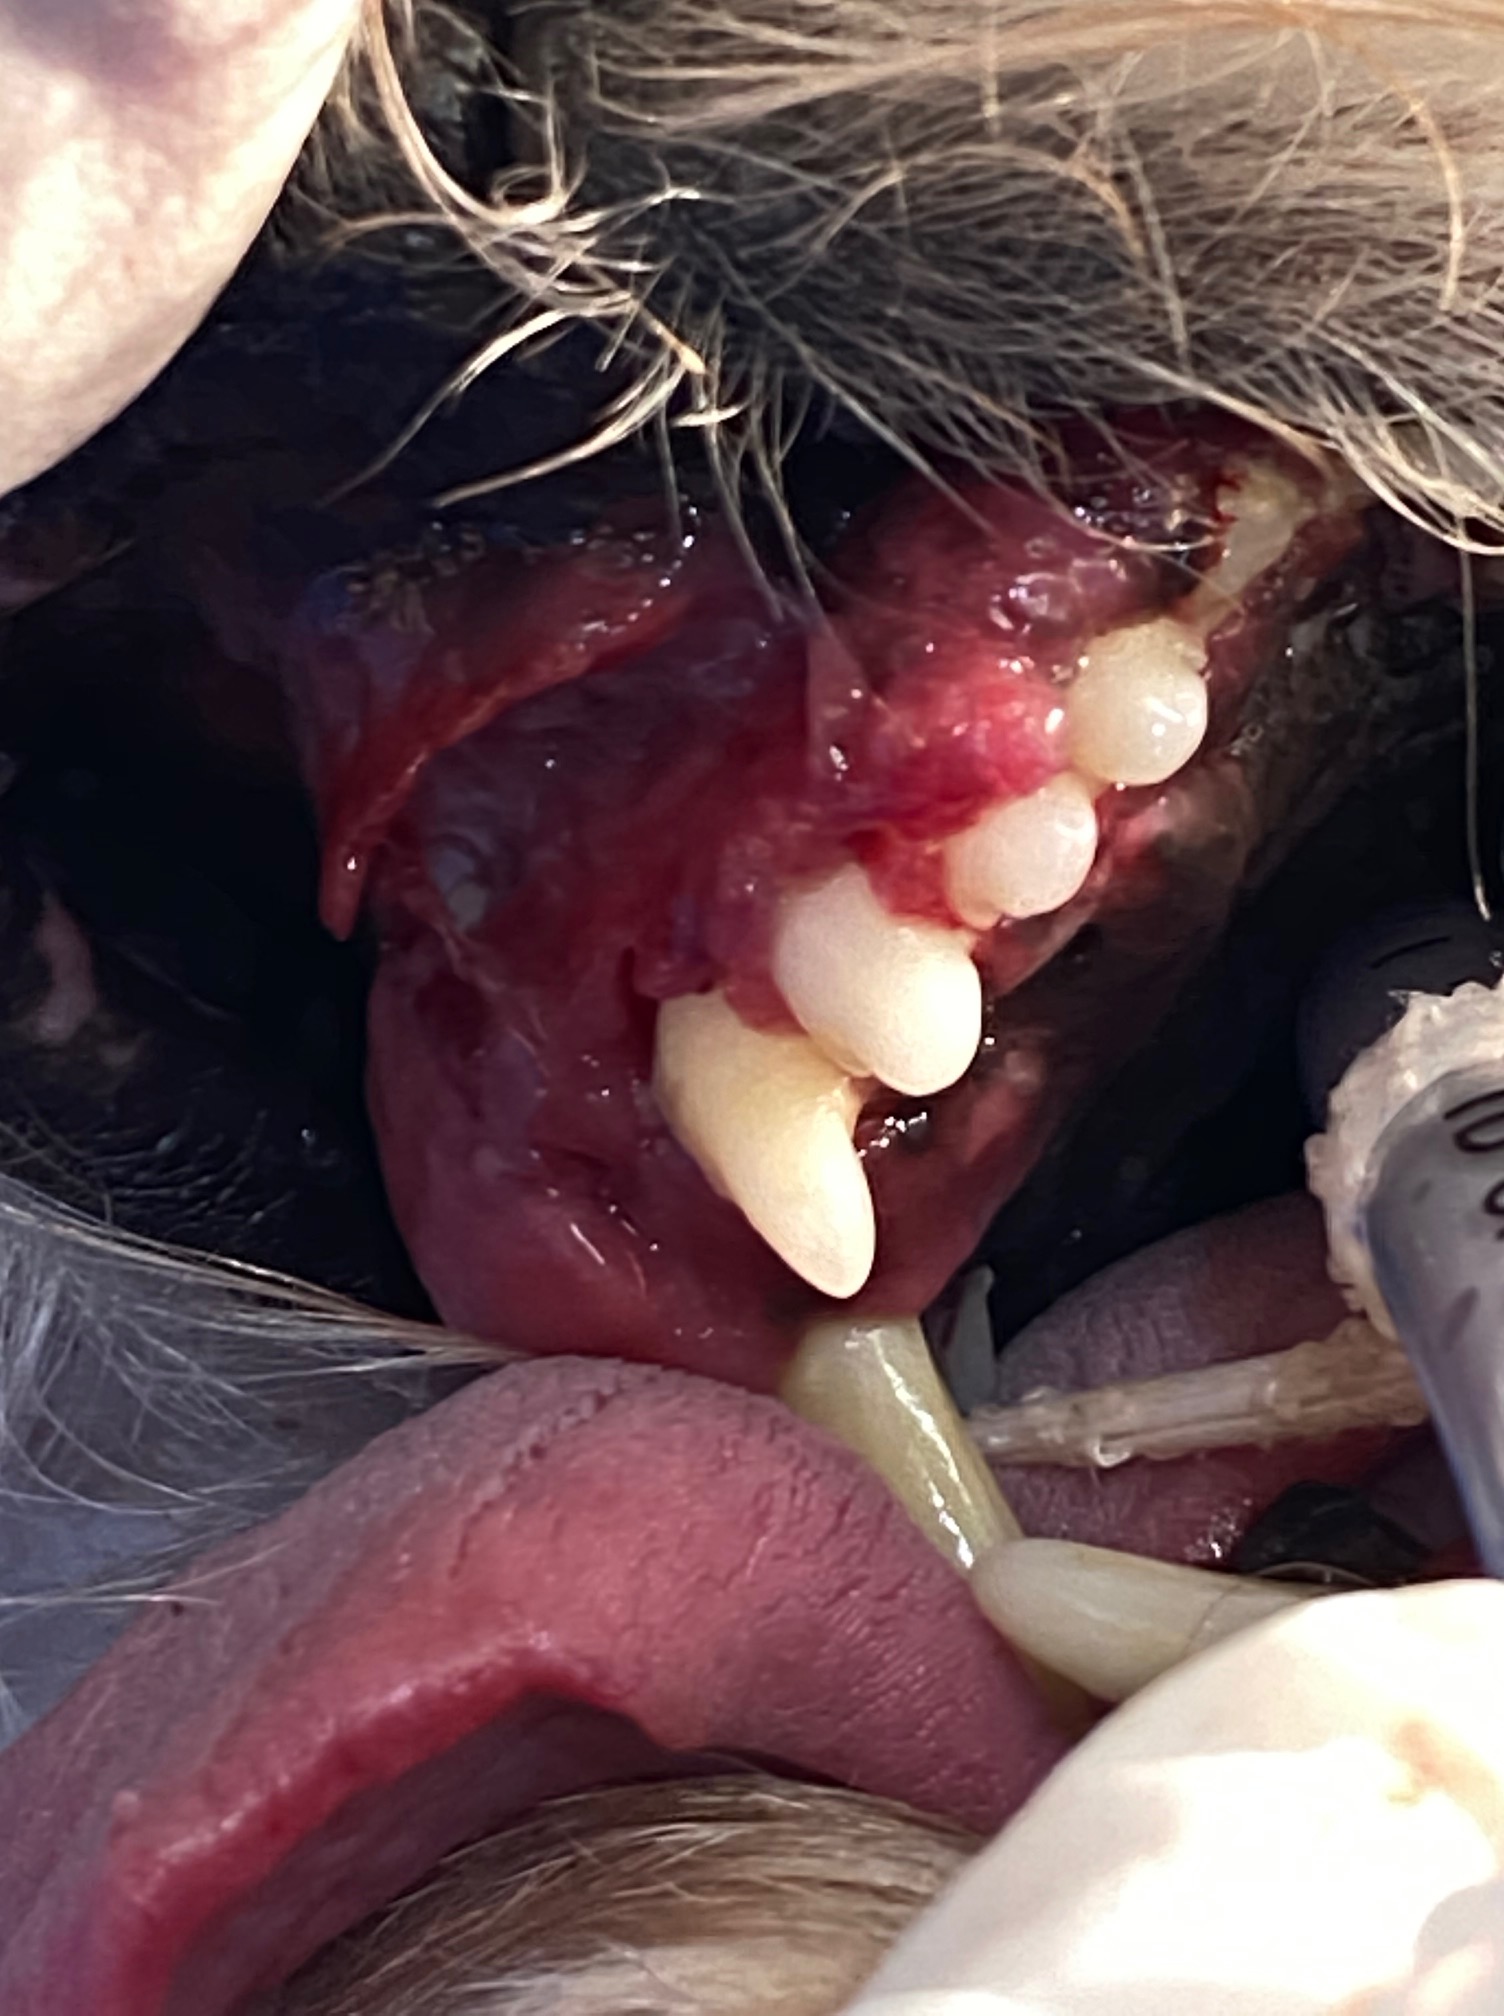

When under GA and the teeth were probed there were 10mm probing depths lingually on both lower canine teeth with severe inflammation of the gingiva bucally and extending below the tongue (see photo). The gingiva around 104 was hyperplastic and inflamed and so friable it just disintegrated when I swabbed it. The other teeth also had increased probing depths. On the xray resorption and ankylosis of many of the teeth can be seen. There was a large lesion in the buccal mucosa possibly where 404 contacted the lip.

A large gingival flap was made and 203, 202, 201, 101, 102, 103, 104, 105 and 106 were extracted using a vet tome, elevators and luxators. The friable gingiva was resected just above the mucogingival margin. The buccal mucosa was bluntly dissected the sutured to the palatal mucosa. 304, 404 and 405 were extracted using the vet tome. The owner was warned pre-operation of the complication of jaw fractured. This did not occur as I used the vet tome, burred away some alveolar bone, used gentle elevation and was patient!. The gingiva between the canines, where the lower incisors had been previously extracted, was also friable. I placed cruciate sutures over the canine sockets to hold the blood clot in place but could not suture the gingiva closed as the tissue was too friable and inflamed. The area between the lower canines was left to heal by secondary intention.